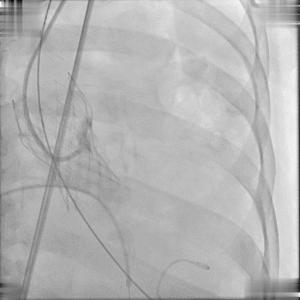

以右侧股动脉为主入路建立双侧入路,Edwards Sapien 3球囊扩张式瓣膜输送系统顺利过弓、跨瓣;随后,行BAV观察患者血流动力学变化情况;

球囊跨瓣

主动脉球囊扩张术(BAV)